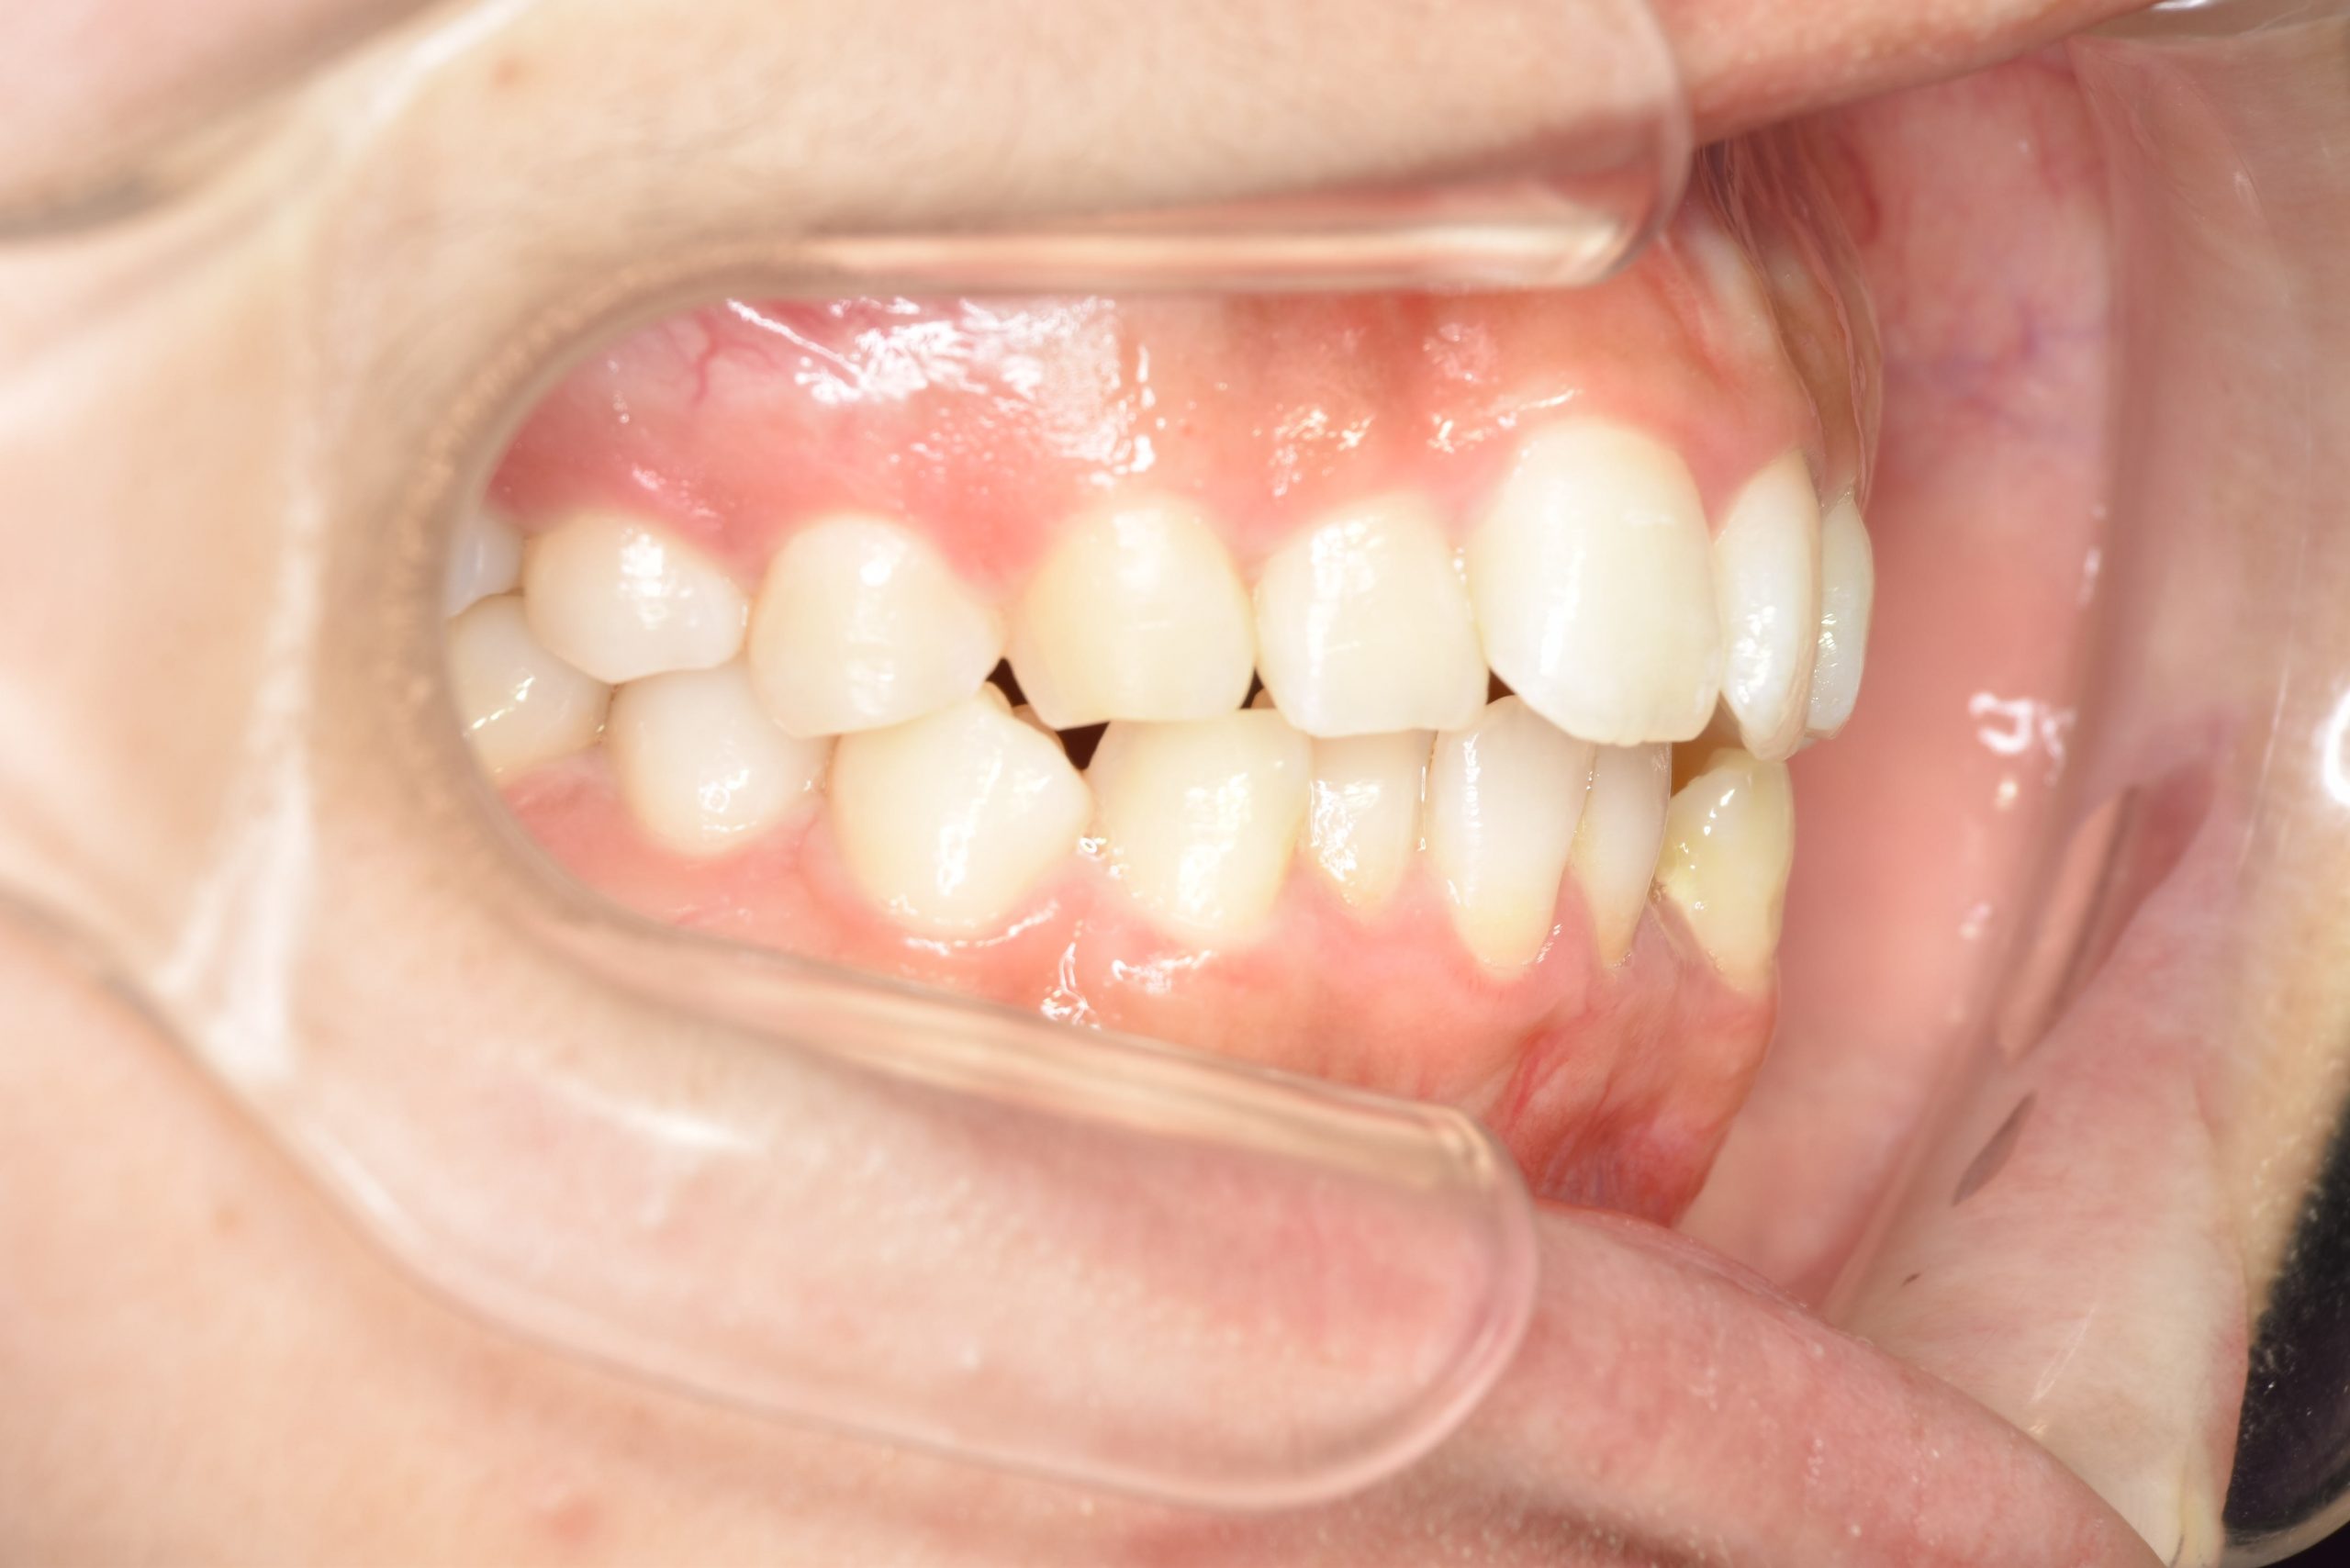

ビフォー

インビザライン矯正治療|症例_315

主訴 食べ物を前歯で噛み切れない|上顎の右側の歯が重なっている|下の歯がガタガタ

施術内容 MSEと下顎リンガルアーチを用いて上下顎骨を拡大した。

その後アライナー型矯正装置(インビザライン)を用いて非抜歯で歯牙を配列した。

口元の突出感、鼻閉症状、鼾は改善された。

治癒期間 1年6ヶ月間